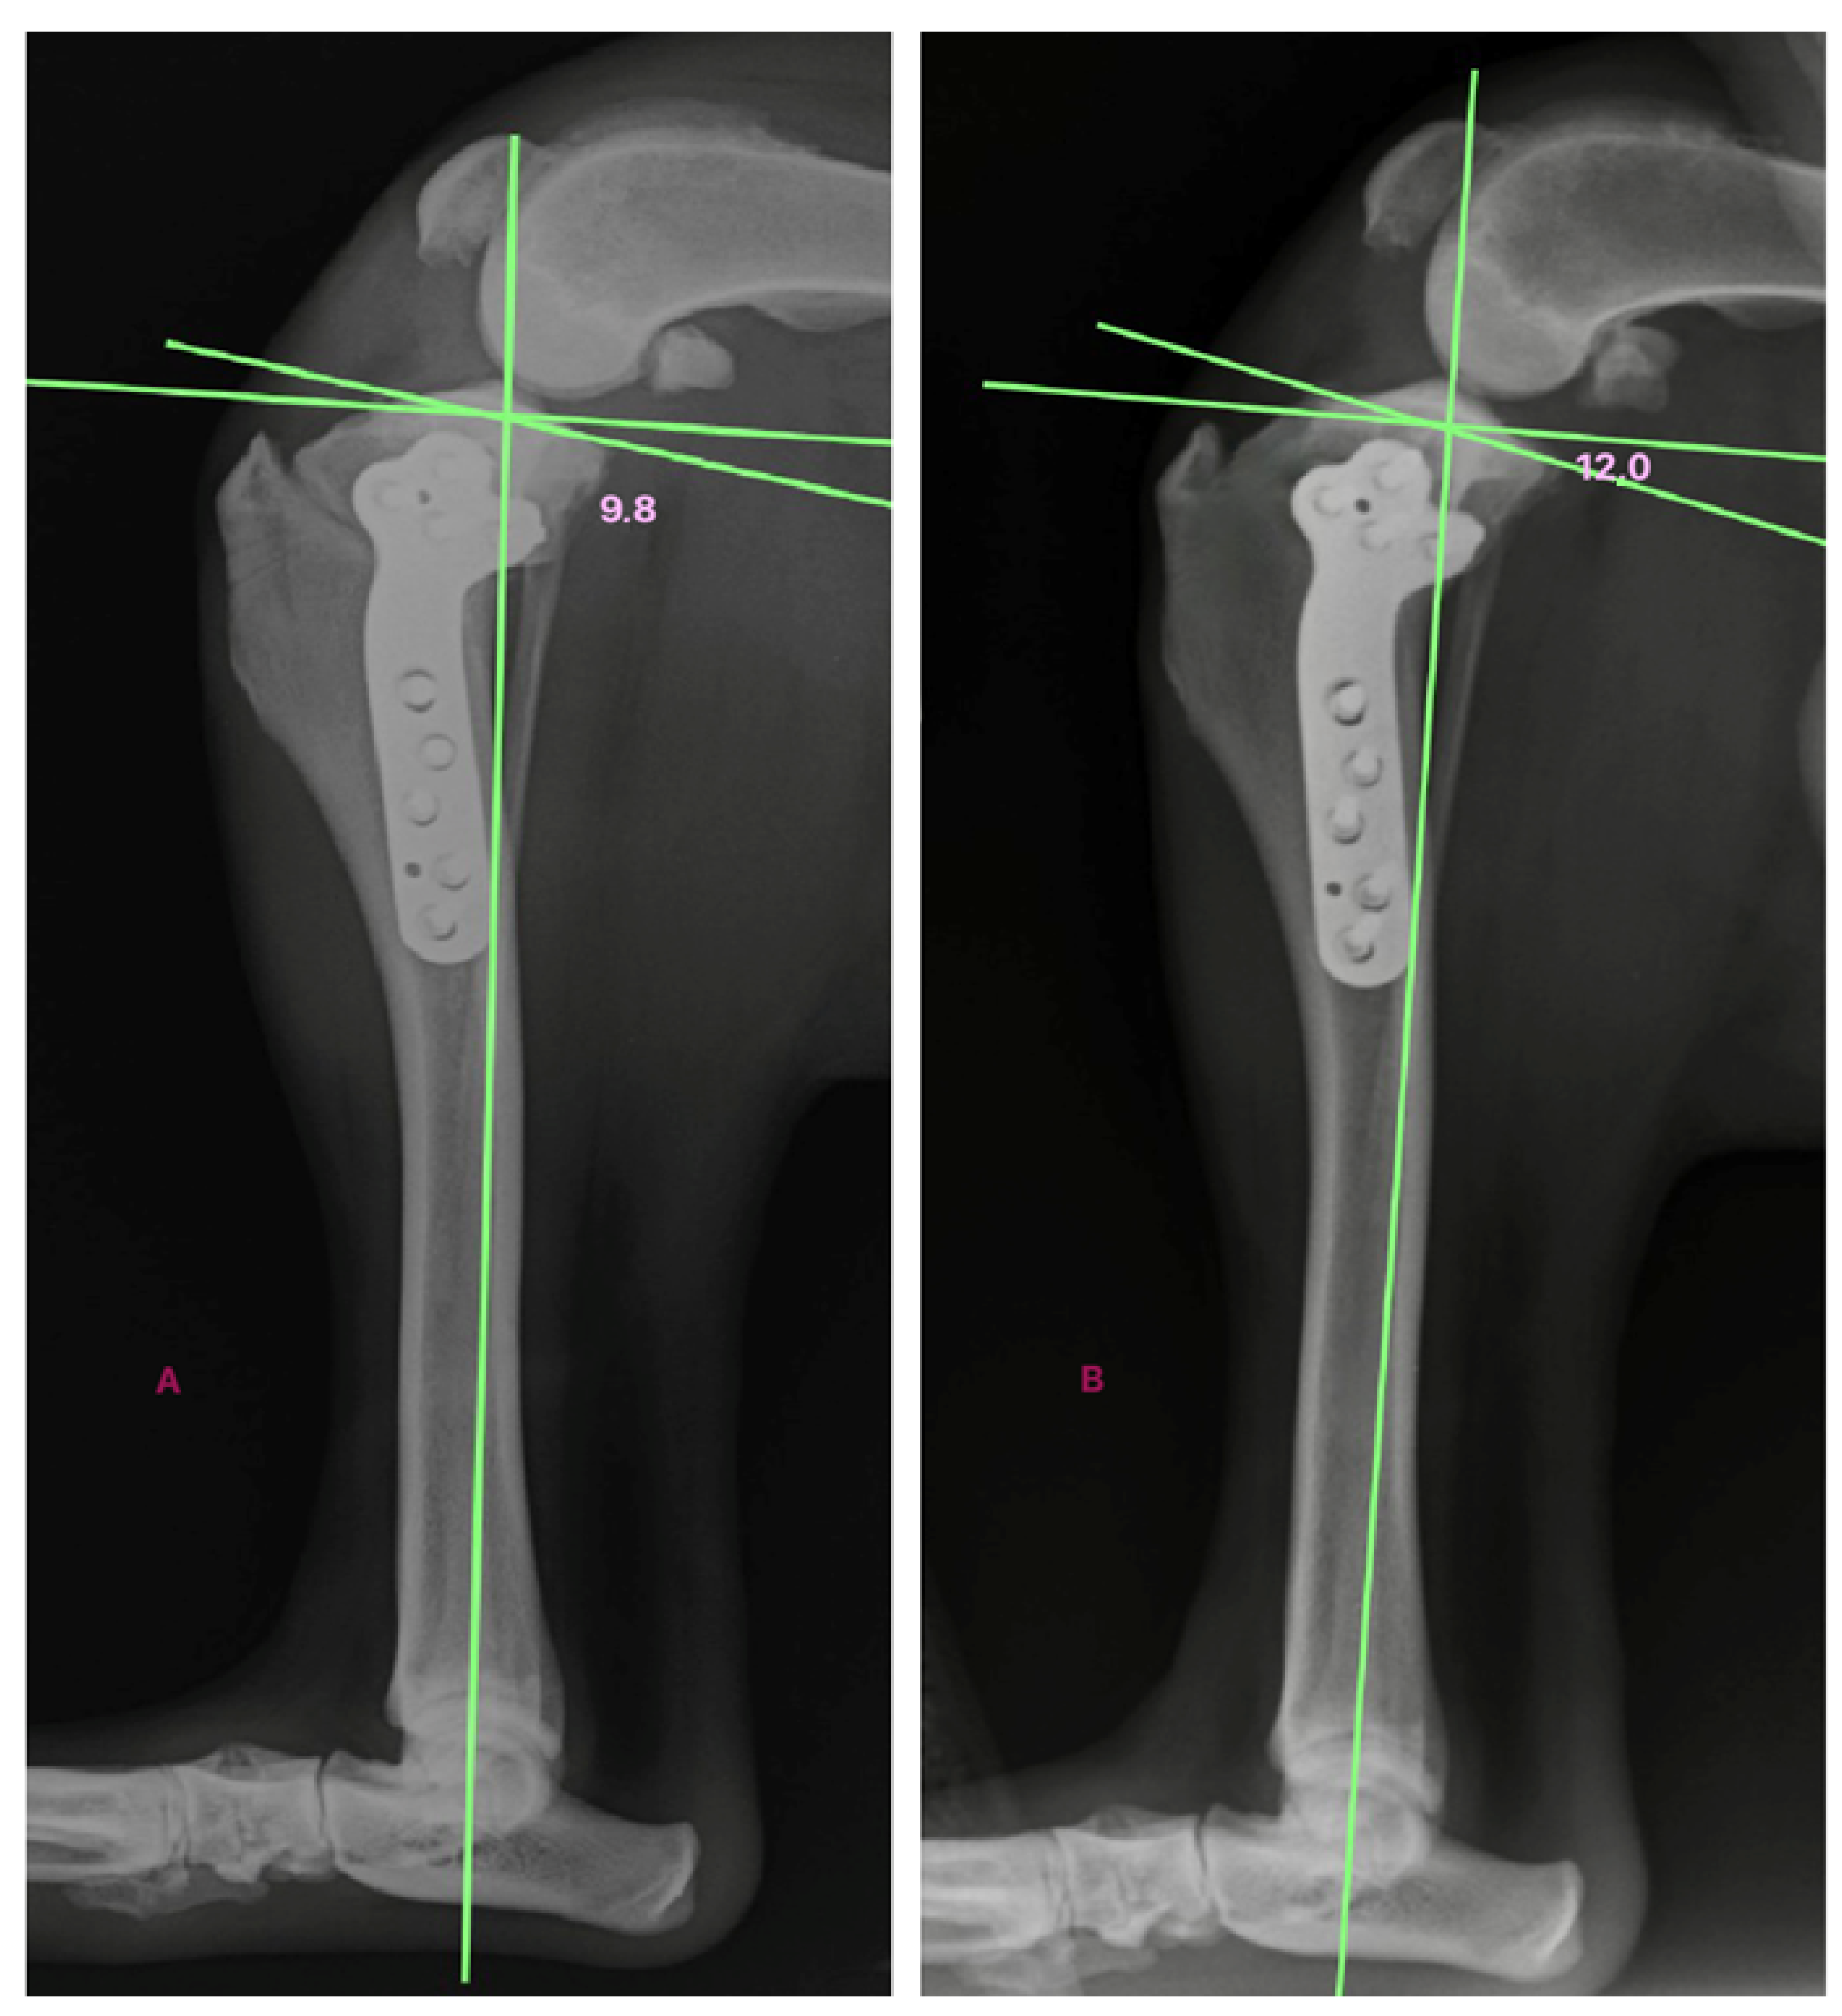

| Dog 5 | 5.4 | 6.7 | 8.6 | 9.8 | 4.4 |

| Dog 6 | 9.8 | 10.9 | 11.8 | 12 | 2.2 |